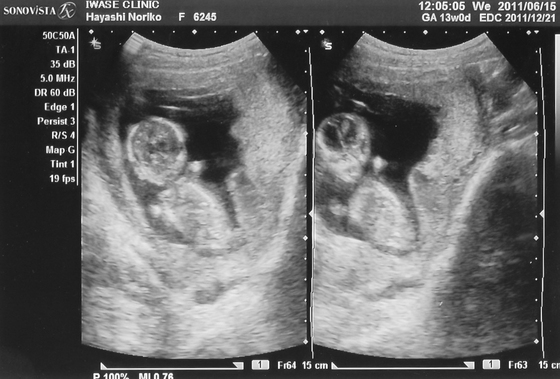

おなかのなか

2011年12月 8日 00:00